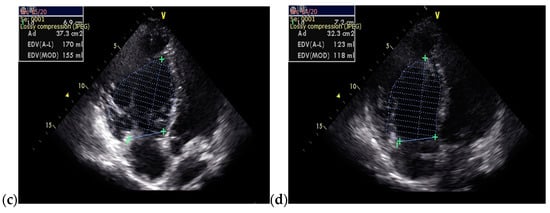

The follow-up TTE evaluation demonstrated a nondilated left ventricle with preserved ejection fraction, dilated right chambers, an increased total volume of RV measuring 339 mL and atrialized RV with a volume of 135 mL, severe functional tricuspid regurgitation, insertion of the septal cusp of the tricuspid valve approximately 2.9 cm from the plane of the tricuspid annulus and ventricular pacing electrode (Figure 12).

Figure 12.

The TTE follow-up evaluation: (a) Apical 4-chamber view: dilated right cavities with a total volume of RV measuring 339 mL; (b) Apical 4-chamber view: atrialized RV volume of 135 mL; (c) Apical 4-chamber view: color Doppler flow revealing severe tricuspid regurgitation; (d) Tricuspid continuous wave Doppler flow: maximum RV-RA gradient = 33.45 mmHg; (e) Apical 4-chamber view: insertion of the septal cusp of the tricuspid valve at approximately 2.9 cm from the plane of the tricuspid annulus; (f) Apical 4-chamber view: end-diastolic left ventricular volume—110 mL. Abbreviations: TTE—transthoracic echocardiography; RV—right ventricle, RA—right atrium.